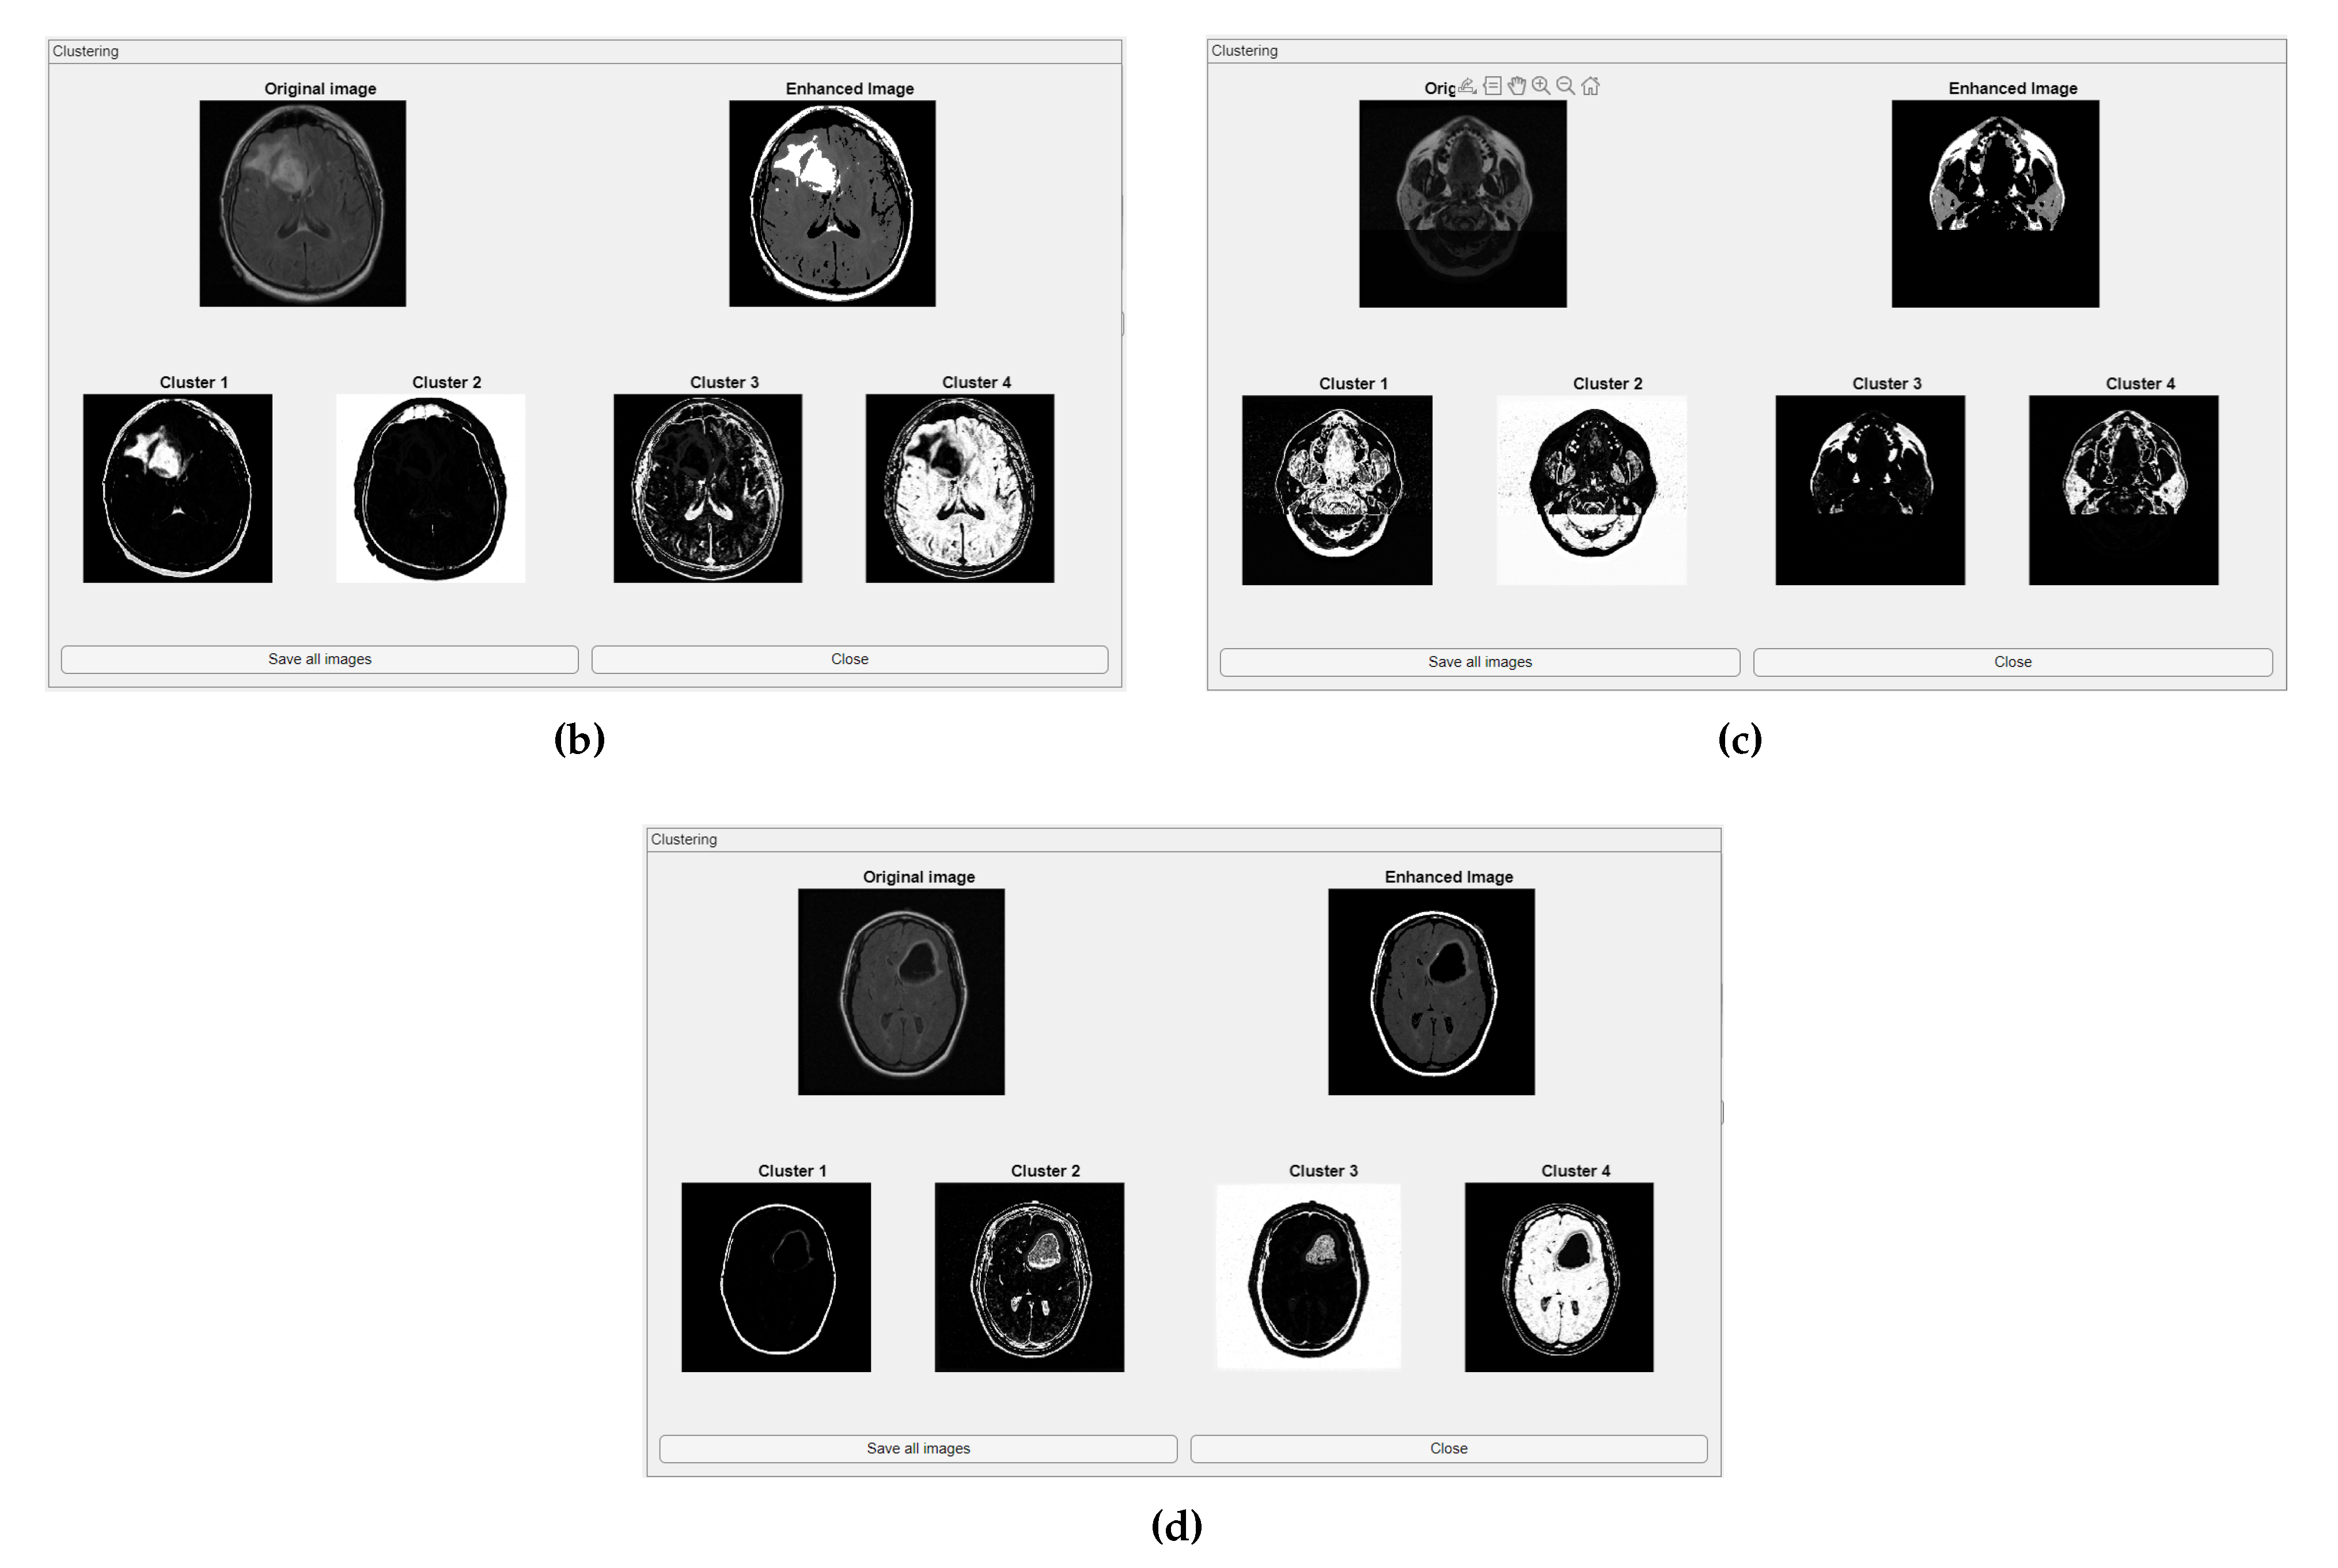

- Original Image: The initial input image from the dataset.

- Enhanced Image: The result after applying image enhancement techniques to improve contrast and feature visibility, likely to support better clustering outcomes.

- Clusters 1 to 4: The segmentation outputs, where the image has been partitioned into four distinct clusters. Each cluster highlights different regions based on pixel similarity, potentially corresponding to anatomical structures, tissues, or specific features of interest within the medical images.

- The clustering module segments images into meaningful sub-regions, enhances contrast, and reveals patterns not obvious in the original images.